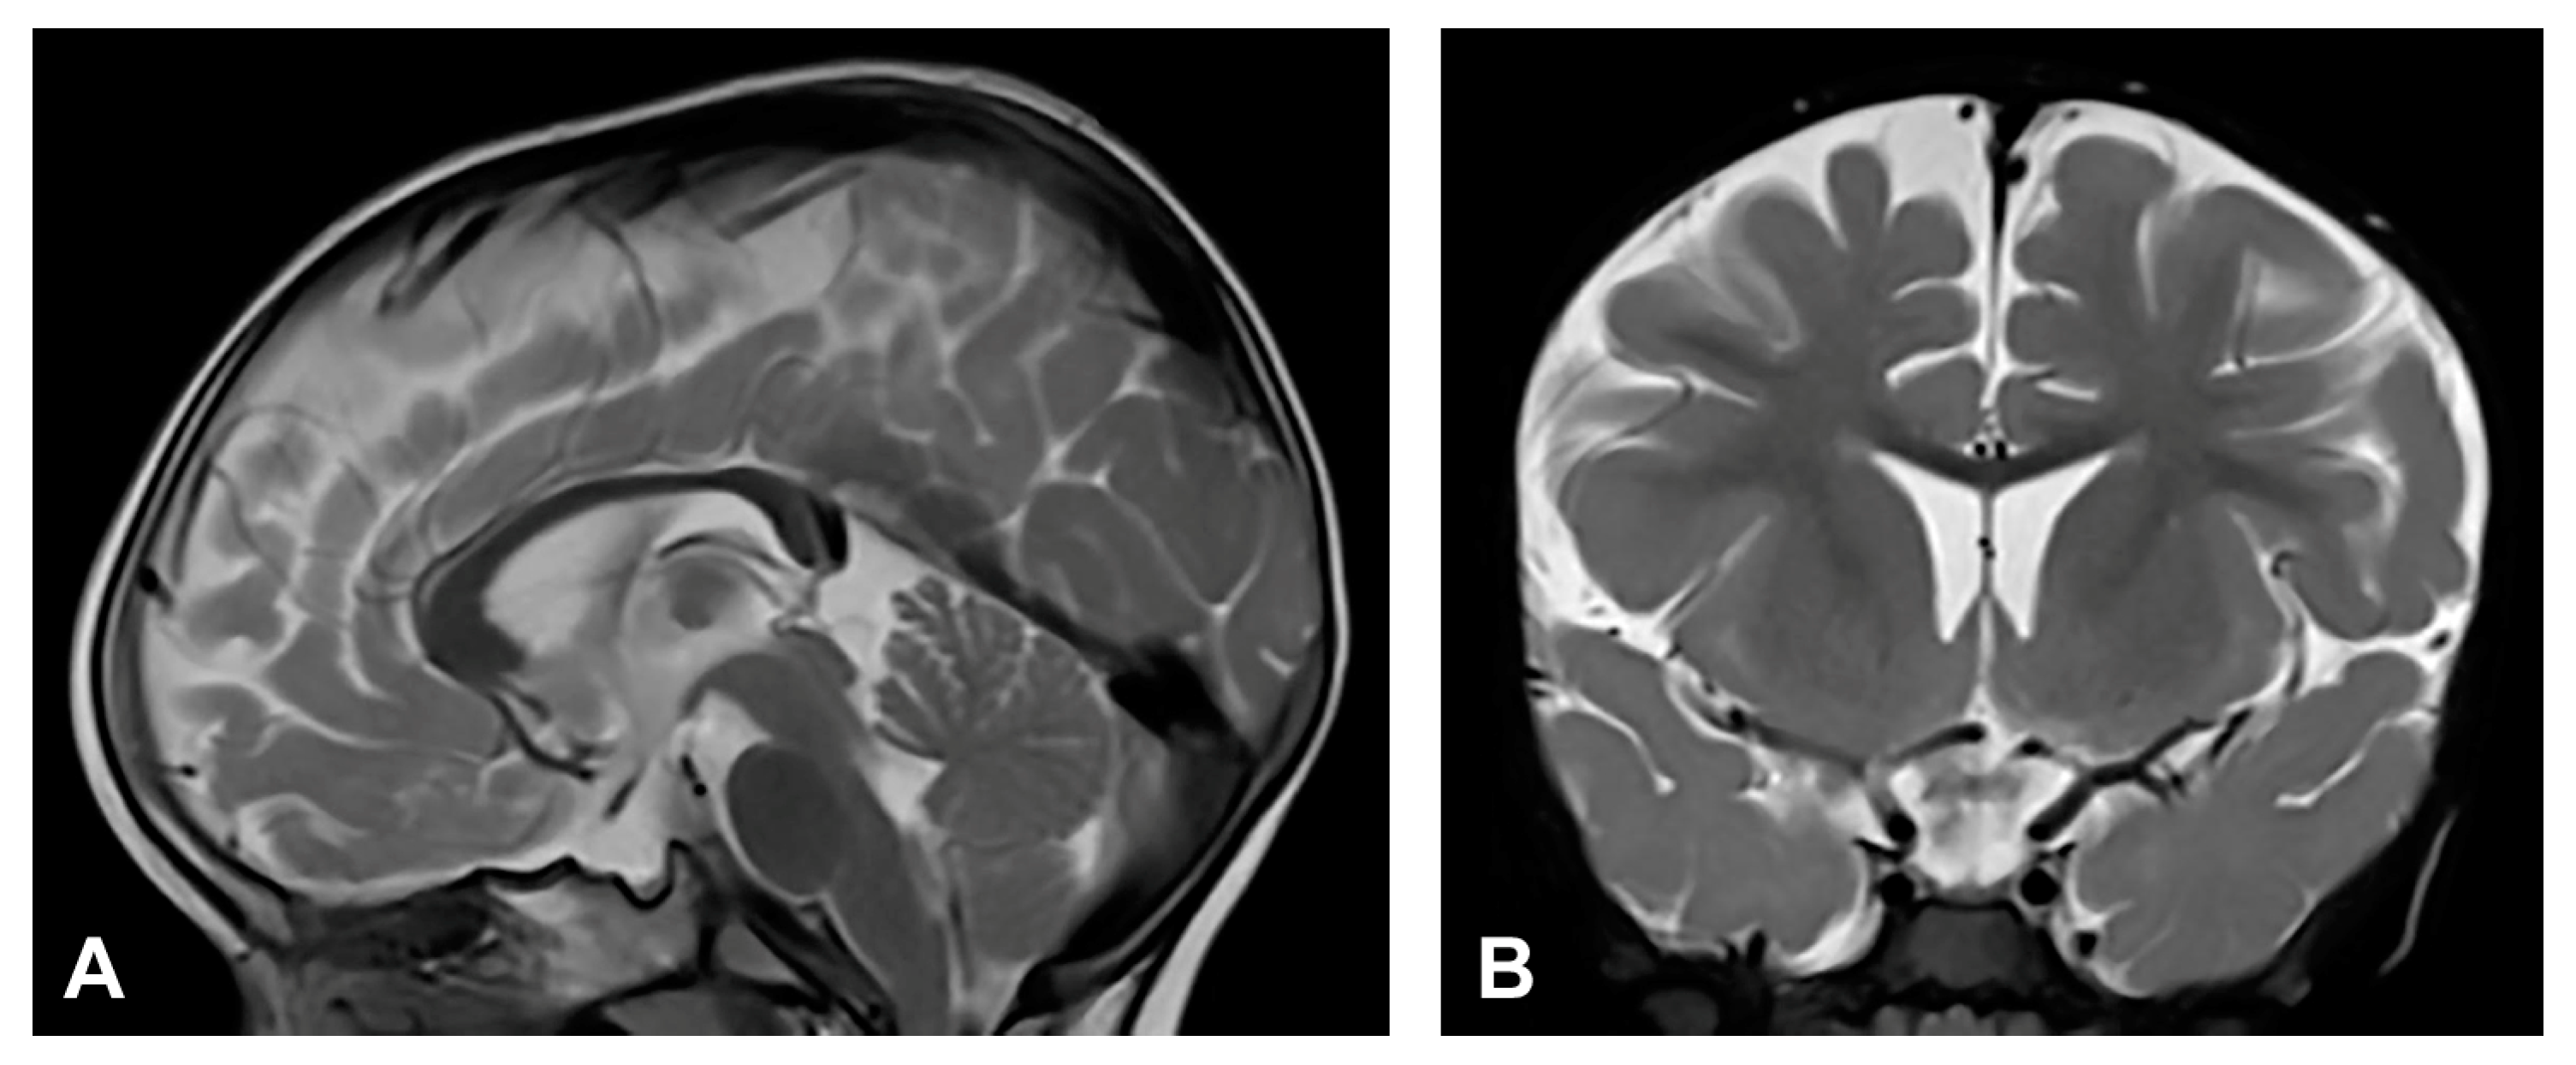

3.2.1. Case 1

3.2.2. Case 2